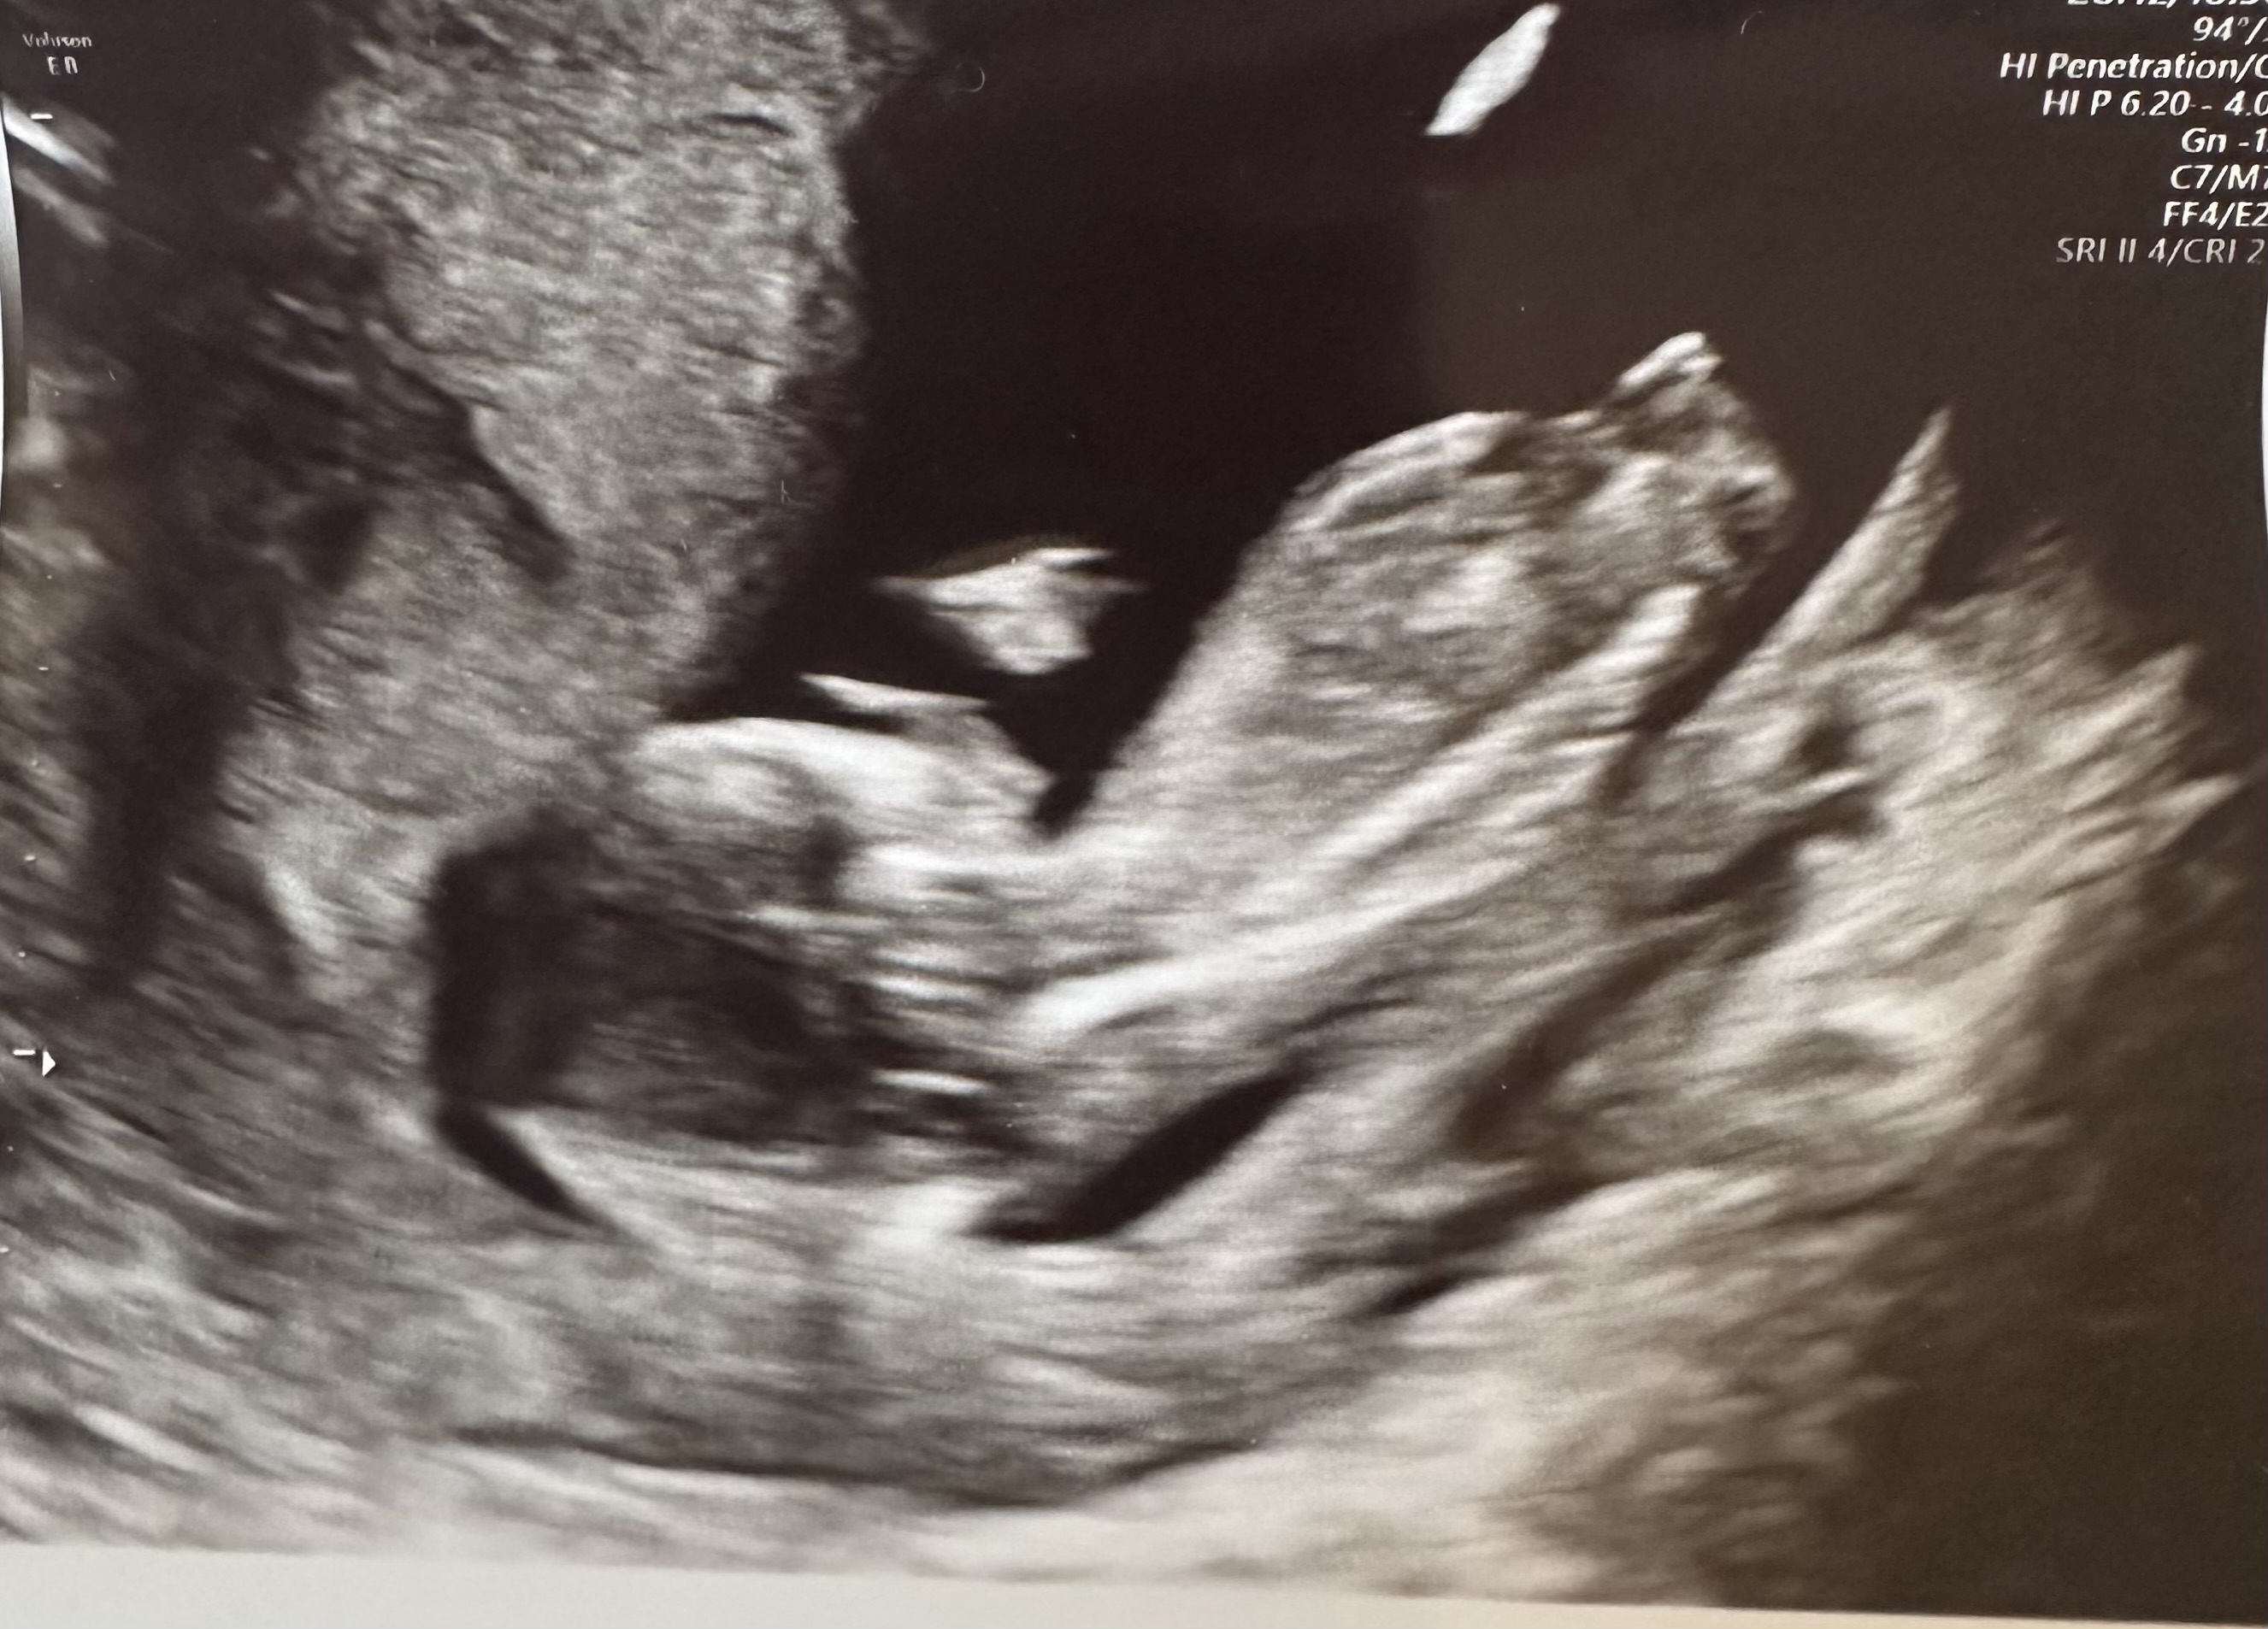

Oktoberbarna 2021♡

Novemberfnuggene 2023

Septembertassene 2026

Tusen takk!! Ja det er virkelig deilig og ha kommet helt hit!Gratulerer så mye med 12+0![]()

Helt herlig å runde den milepælen der

Nå har jeg liksom trua på at dette går veien